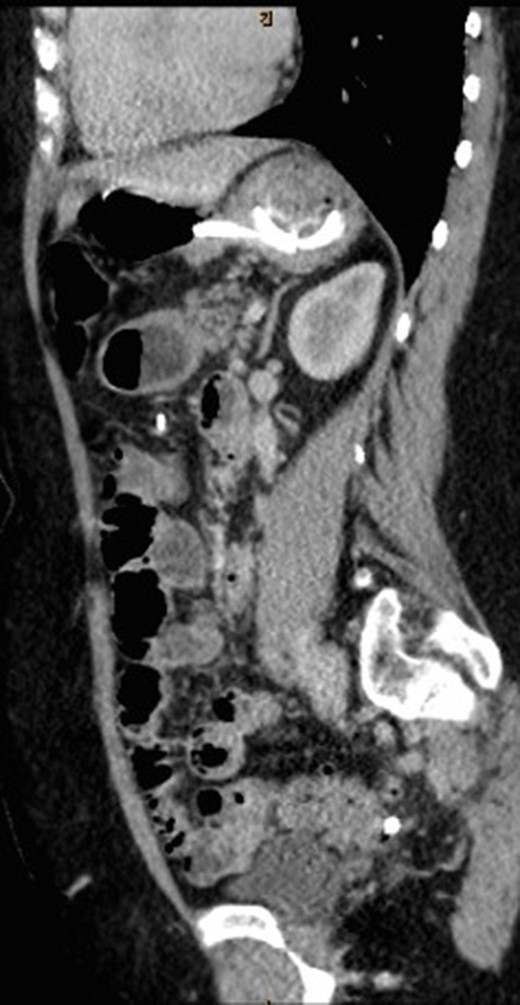

Sagittal view of CT abdomen showing the gastric band tubing eroding into posterior wall of transverse colon and exiting inferiorly.